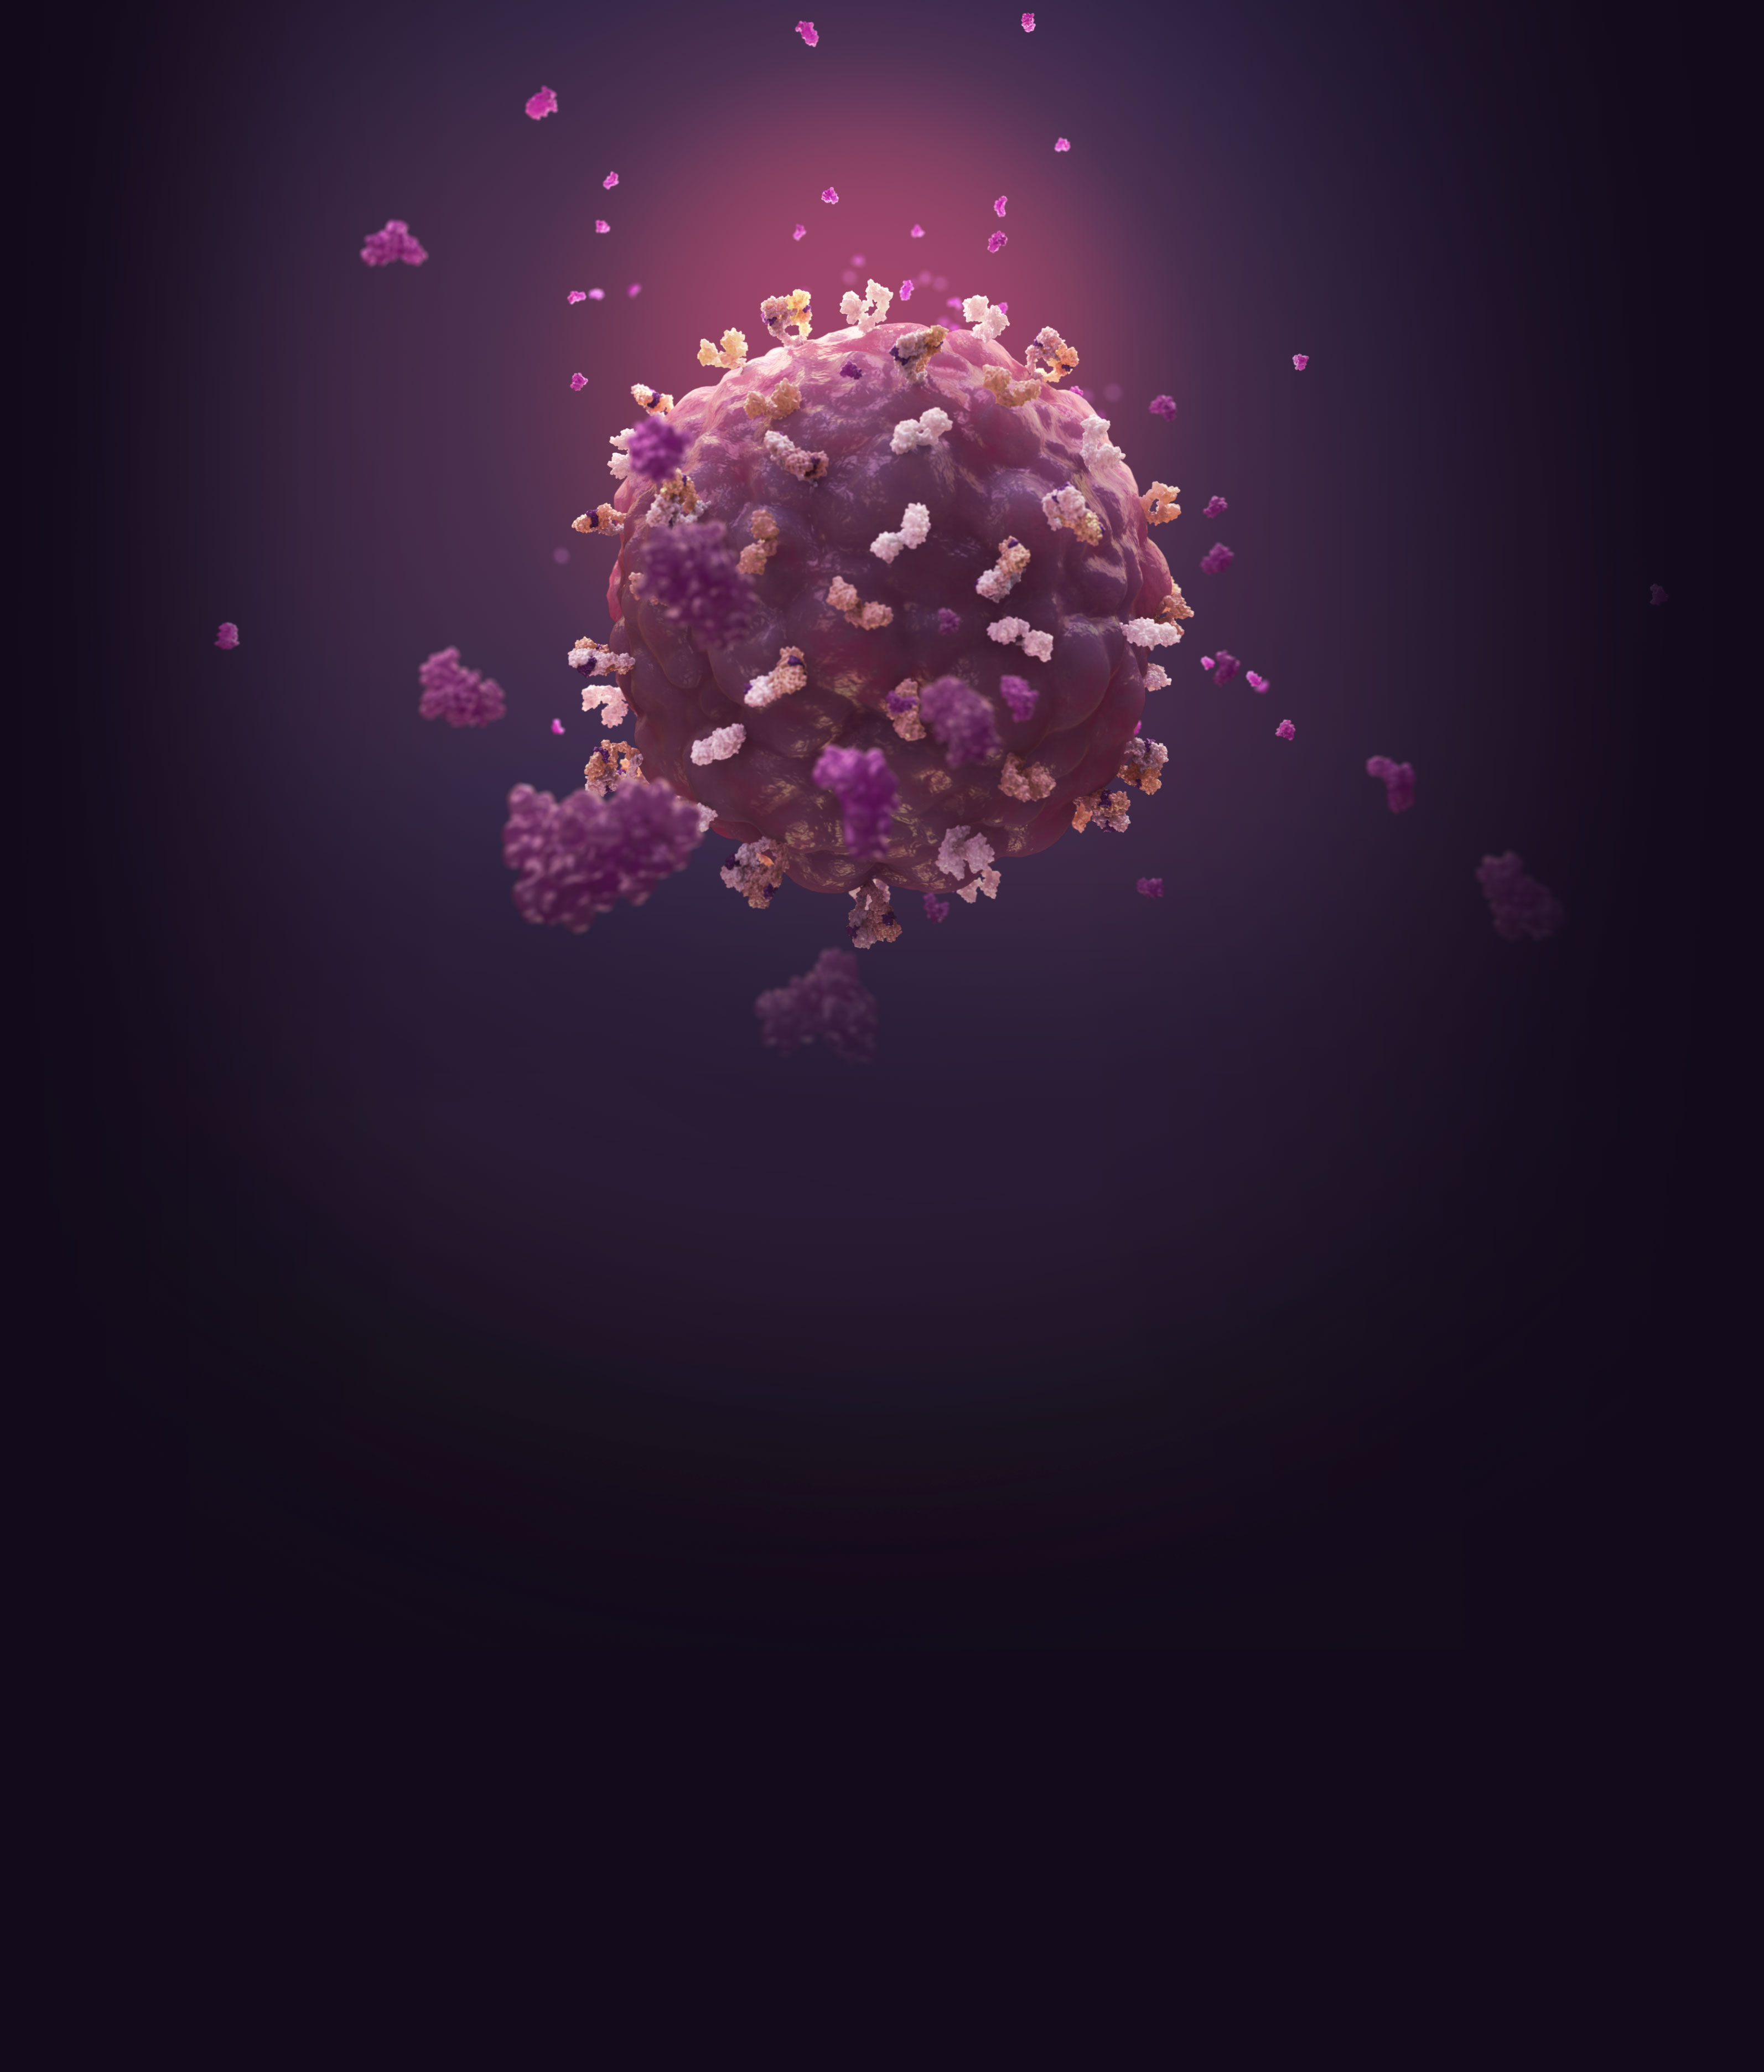

HER3/ERBB3 is one of the four members of the HER family of receptor tyrosine kinases1,2

- All four members of the HER family share a common molecular structure and play a role in normal cell biology1–4

- Members of the HER family are expressed widely in numerous cell types, including epithelial, neuronal, and mesenchymal cells1

- HER3 activation depends on heterodimerization with another receptor to induce downstream signaling pathways4

- Although HER2 is generally its preferred dimerization partner, HER3 can dimerize with other receptors in the HER family2,4

- HER3 also dimerizes with some non-HER family receptors, including MET and FGFR24,5

HER3 dimerization and activation are involved in normal cell physiology1

- In normal physiology, binding of the ligand (heregulin, a neuregulin family member) leads to dimerization1

- After dimerization, HER3 relies on its dimer partner’s tyrosine kinase activity, which can then phosphorylate one or more of the tyrosine residues on its intracellular kinase domain4, 5

- This leads to activation of pathways that regulate normal cell division, proliferation, and differentiation4,5

HER3 expression is higher on tumor cells compared with normal healthy cells22

HER3 in Cancer Cells

- HER3 activation can sustain several oncogenic signaling pathways, including PI3K/Akt, MAPK, JAK/STAT, and SRC1,2,23,25

- Amplification/mutation/overexpression of HER3 ligands and dimerization partners, including HER and non-HER RTKs, such as MET, can promote bypass signaling through activation of these signaling pathways2,25−29

- Increased HER3 signaling or expression may play a role in the initiation of signaling activity leading to increased cellular proliferation, invasion, and migration in multiple tumor types, including breast, HNSCC, colorectal, and lung cancers1,2,4,31,32